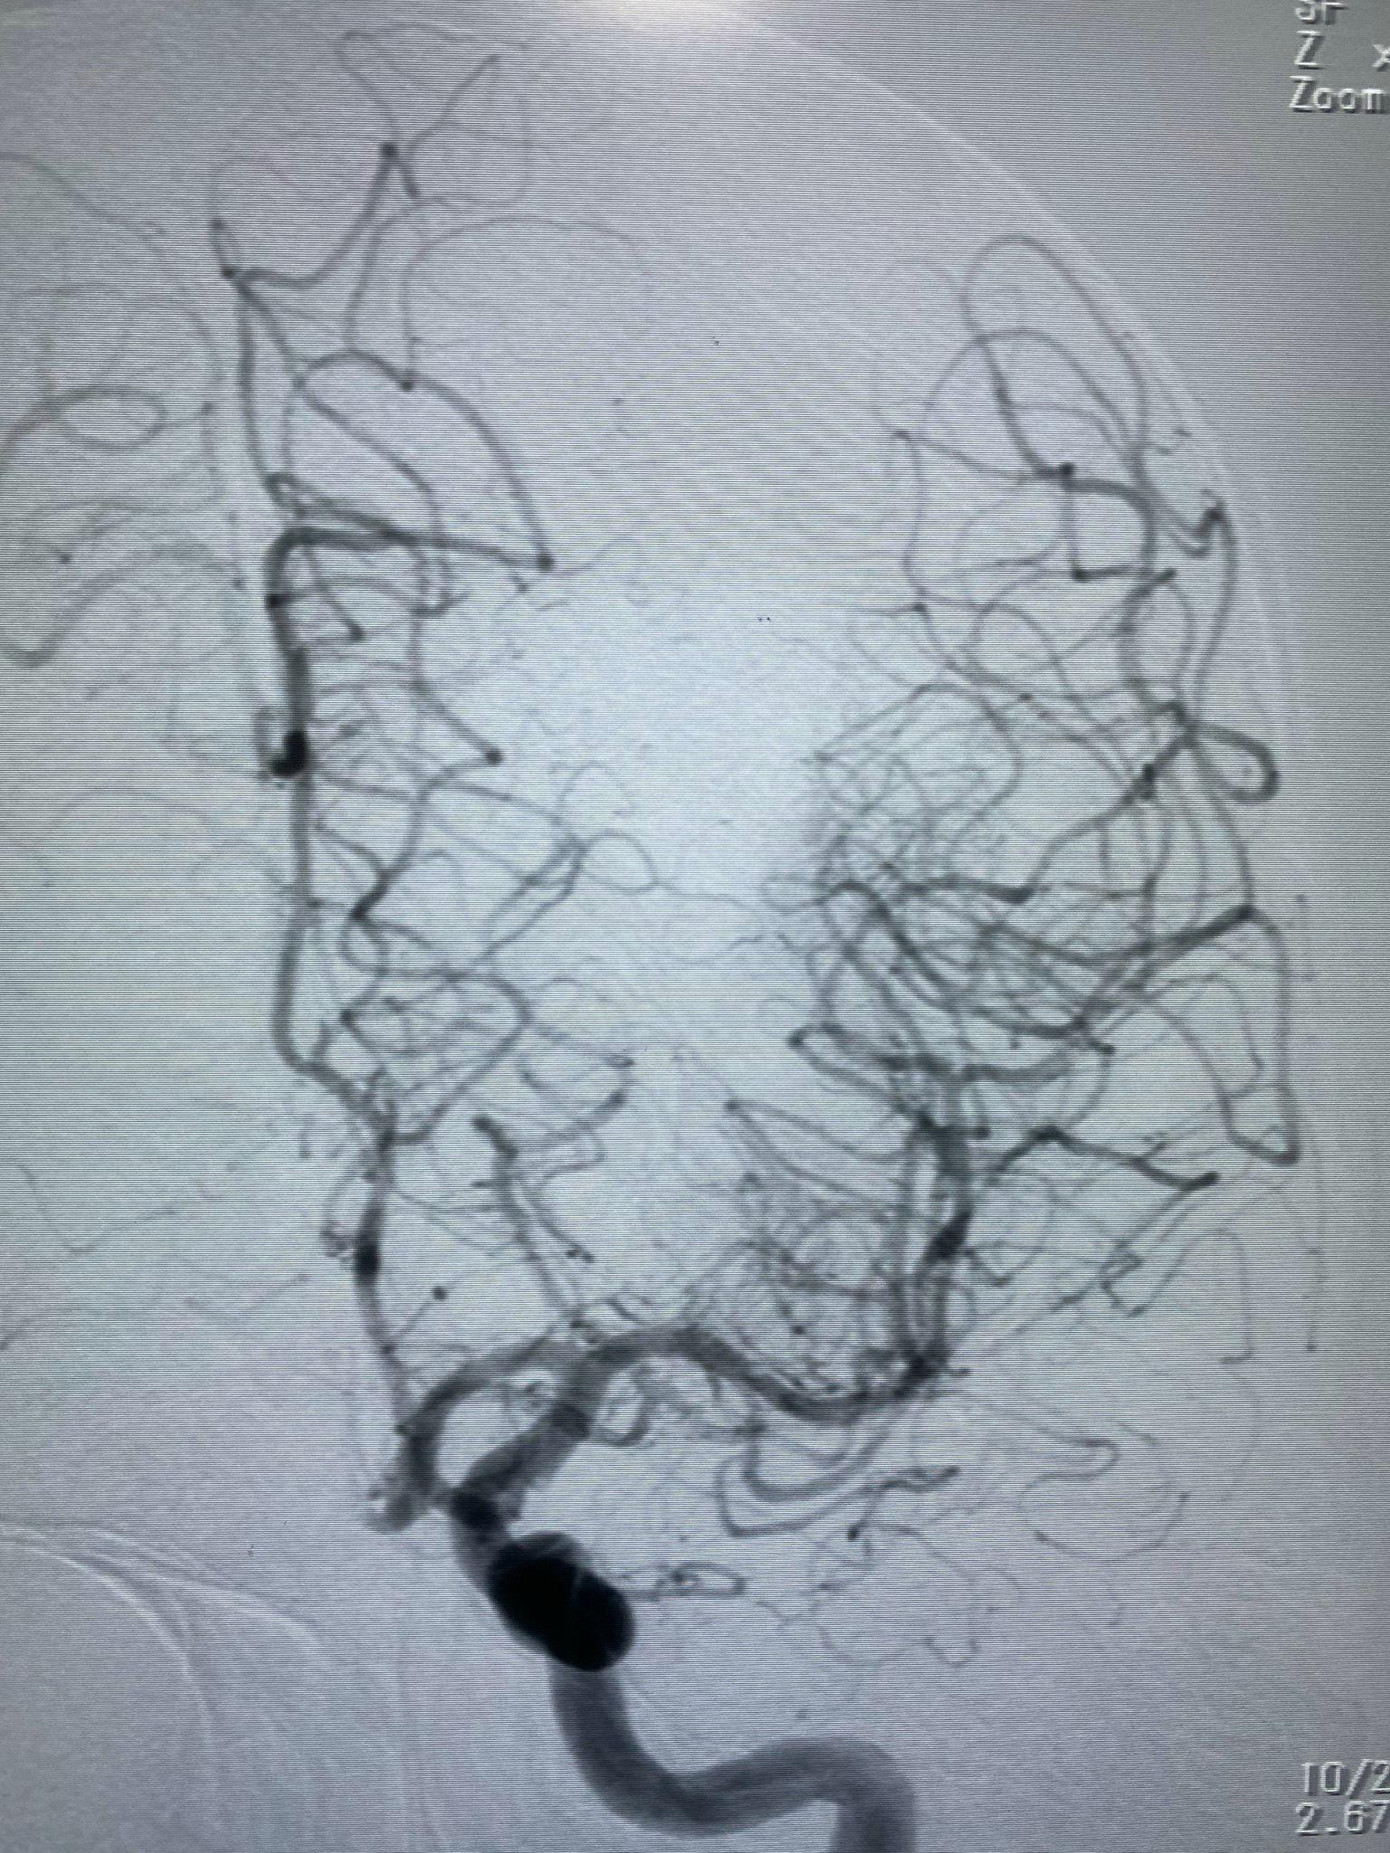

| Mạch máu não của bệnh nhân sau khi được bác sĩ can thiệp tái thông |

Bệnh nhân đối mặt với tình trạng đột quỵ rất nặng, nguy cơ tử vong cao. Các bác sĩ đã hội chẩn nhanh và quyết định can thiệp tái thông động mạch não giữa khẩn nguy. Sau 20 phút khẩn trương trong phòng can thiệp, ê kíp đã lấy thành công cục máu đông, tái thông mạch máu bị tắc cho người bệnh. Ngày 23/9 sau 5 ngày can thiệp, sức khỏe bệnh nhân đã bình phục tốt, có thể cử động chân tay gần như bình thường.